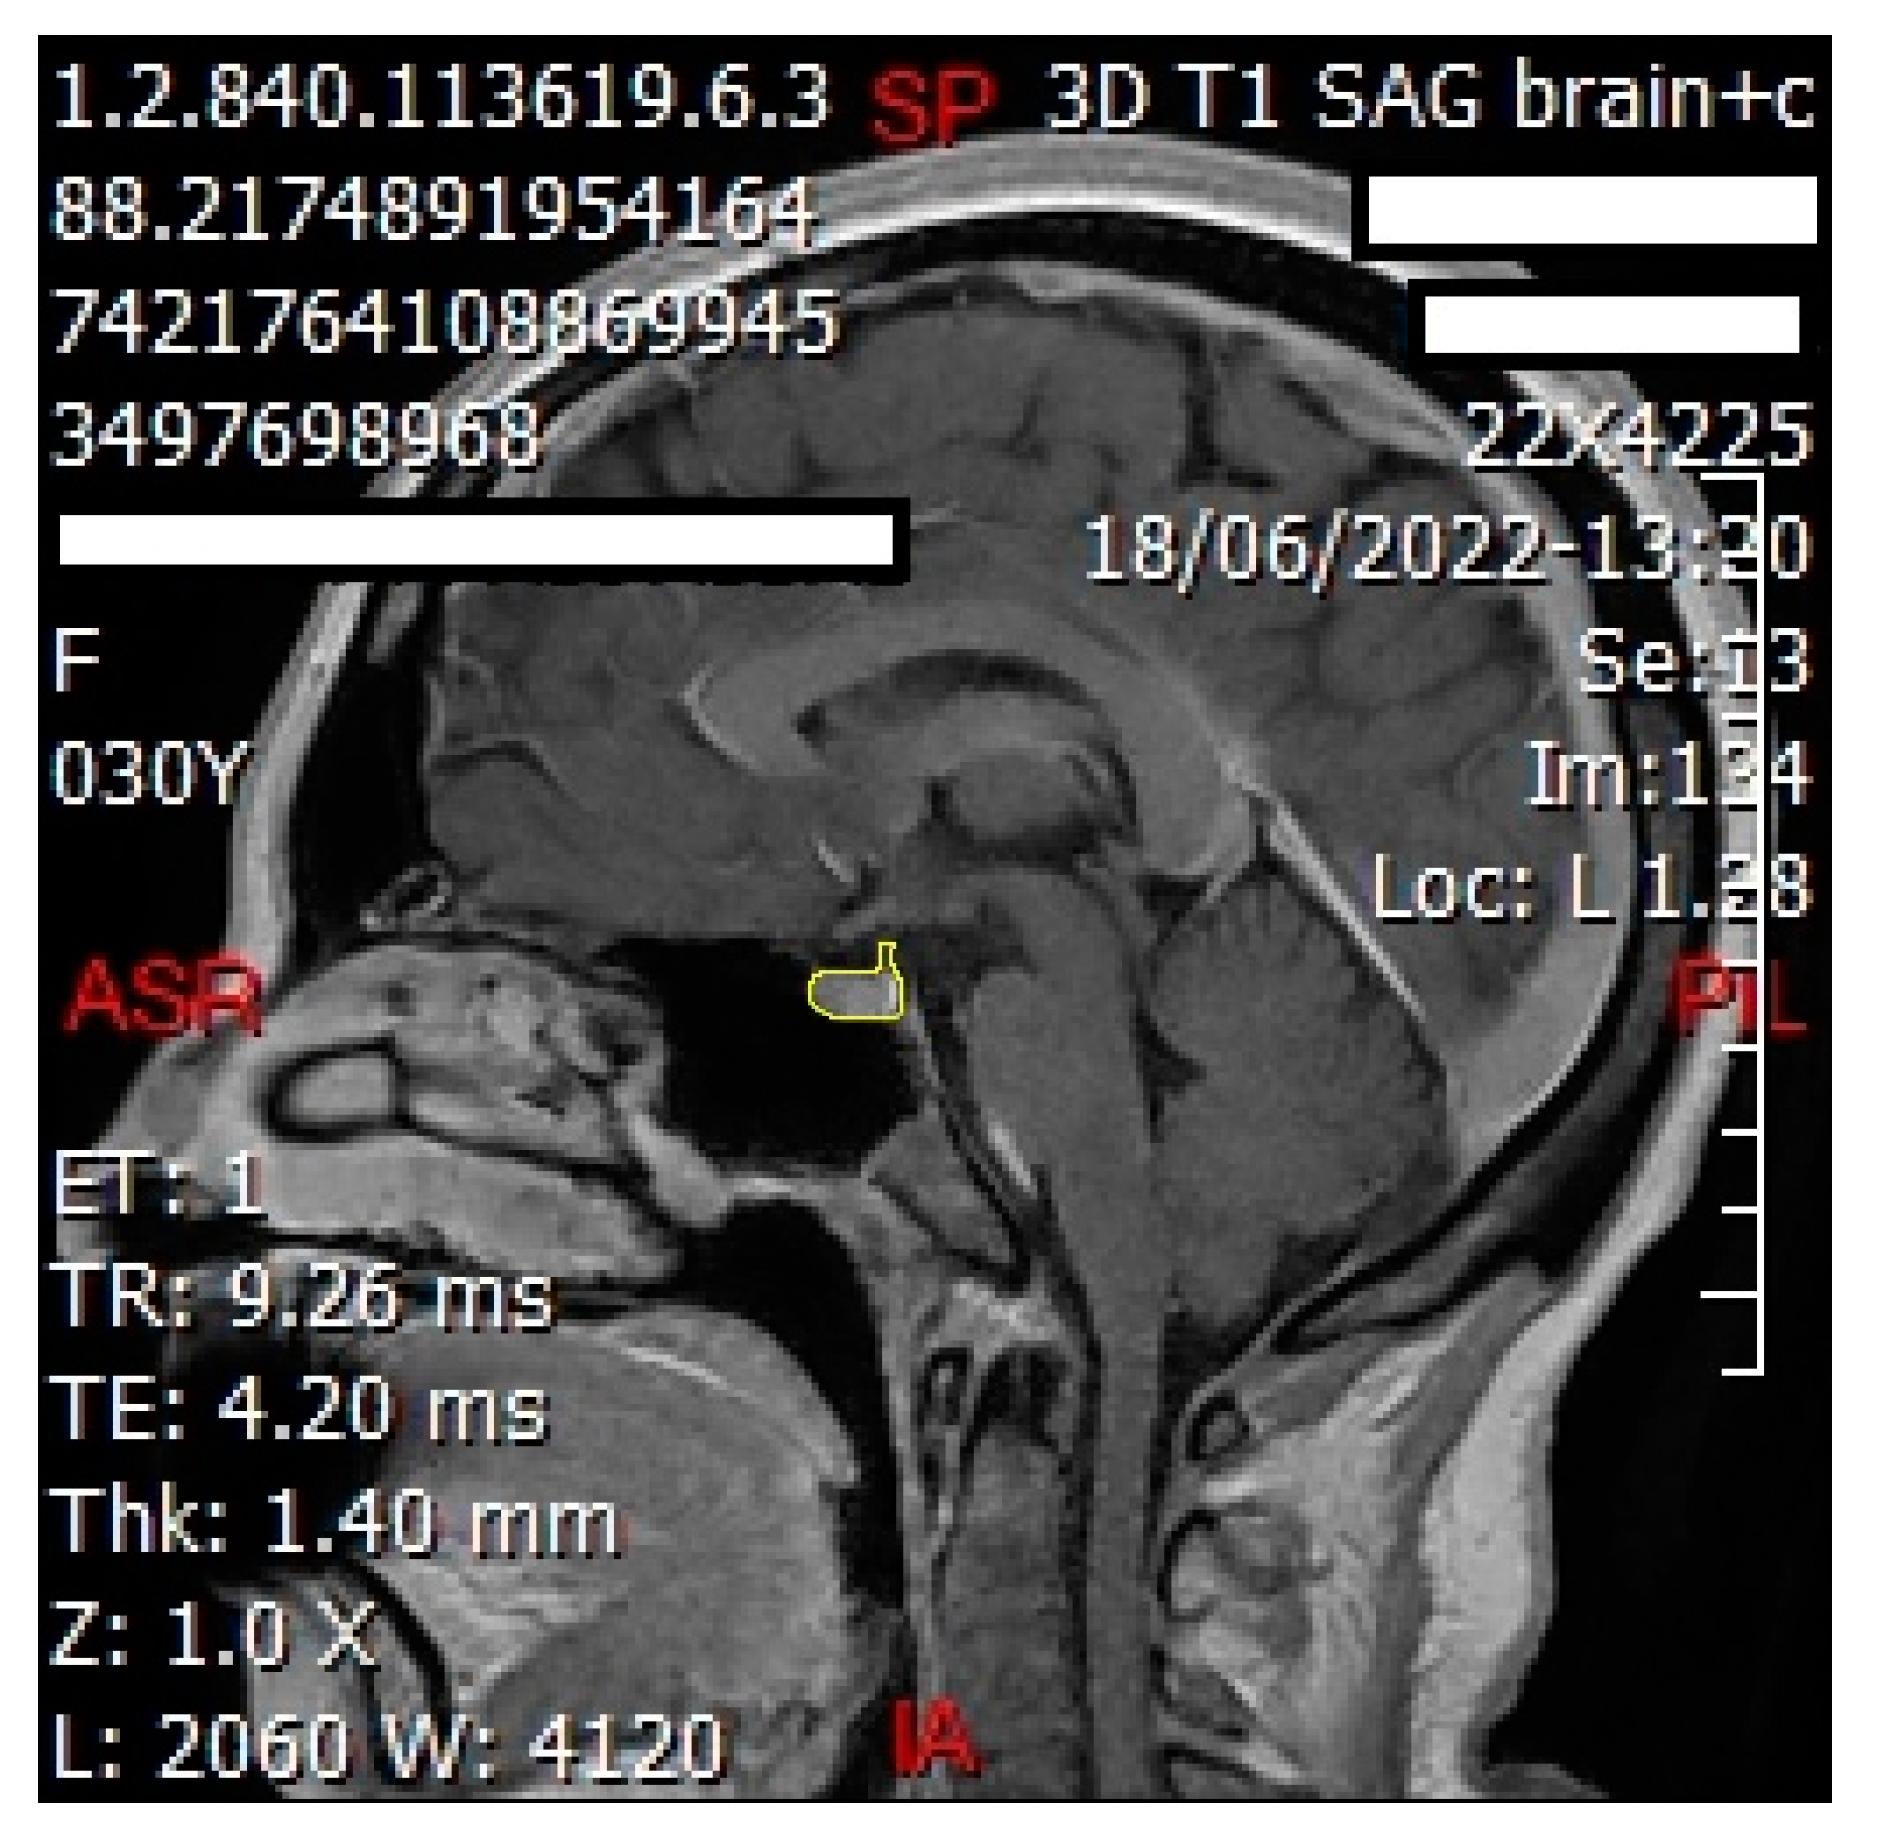

2.5. Volume Measurement

Using Three-Dimensional Slicer software (version 5.0.2 r30822/a4420c3), we analyzed contrast-enhanced weighted-T1 sequences from each participant’s MRI to measure the volumes of the pituitary gland and the pons. Under the supervision of a certified radiologist to ensure accuracy, we manually delineated the borders of the pituitary gland using the ‘Segment Editor’ tool, covering its entire surface area (Figure 1). This delineation was performed across all imaging planes (sagittal, coronal, and axial), and the ‘Grow from seeds’ functionality was employed to refine and smooth the selection. Subsequently, ‘Segment Statistics’ provided measurements of pituitary gland volume in cubic millimeters, including voxel counts. The same procedure was applied to delineate and measure the volume of the pons. To facilitate comparative analysis, we calculated the normalized volume of the pituitary gland by dividing its volume by that of the pons.

Figure 1. Using 3D Slicer software (version 5.0.2 r30822/a4420c3), the pituitary gland (shown in green area) was delineated and covered all its surface areas on axial (a), coronal (b), and sagittal (c) sections; (d) shows the pituitary gland in a 3D view.